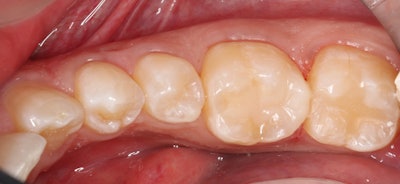

At this point, the Panavia SA Cement Universal was injected directly onto the onlay and seated. There was no need to apply a separate primer to the intaglio. It was then tack cured for 3 seconds (Bluephase G4, Ivoclar Vivadent, after which the excess could be peeled off, making for an easy cleanup.

Unlike most resin cements, Panavia SA Cement Universal provides virtually equal bond strengths whether light cured or self-cured for 2 to 4 minutes. The strength of the self-cure bond is within 1 megapascal of that achieved with light curing.

By choosing to proceed with an indirect restoration made of a hybrid ceramic block and bonding with Panavia SA Cement Universal, this procedure offered many advantages for both the clinician and the patient. This approach provided a superior restoration in terms of the hardness and lack of voids or porosities due to the restorative material. It also conserved tooth structure. Further, since it was an indirect restoration, C-factor stresses were greatly reduced, which will provide a durable, well-sealed restoration.